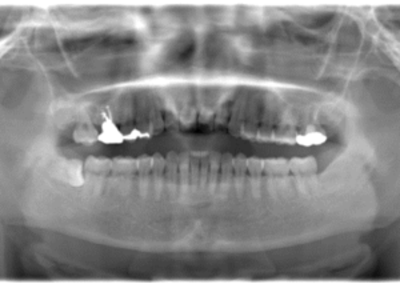

初診時レントゲン(パノラマ)

初診時パノラマX線写真と口腔内写真。

右上6に腫脹と排膿がみられた。